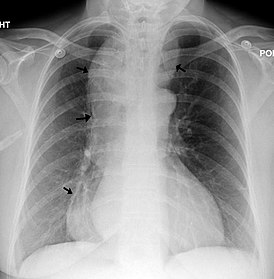

- рентгенологическое контрастное исследование – пациенту предлагают проглотить порцию контрастного вещества (сульфата бария), после этого делают серию рентгенологических снимков. По ним выявляют скорость перемещения сульфата бария по пищеводу и освобождения от него конечного участка пищевода;

- Рентгенография грудной клетки. Обследование начинается именно с данного исследования. В случае выявления на рентгенограмме тени расширенного пищевода с жидкостным уровнем назначается рентгенография пищевода, предполагающая предварительный прием бариевой взвеси. Если имеет место ахалазия кардии, то становится заметным сужение конечного отдела пищевода, а также расширение участка, располагающегося выше.

У больных с кардиоспазмом при рентгенологическом исследовании выявляют усиление моторики пищевода с выраженными сегментарными сокращениями, при ахалазии кардии — снижение моторной активности пищевода (отсутствие первичной перистальтики в дистальных 2/3 пищевода).

Рентгенологическими признаками кардиоспазма являются расширение пищевода в той или иной степени с наличием «узкого сегмента» в терминальном его отделе. Стенки пищевода, в том числе и в суженной части, сохраняют эластичность. В расширенном пищеводе натощак определяется значительное количество жидкости.